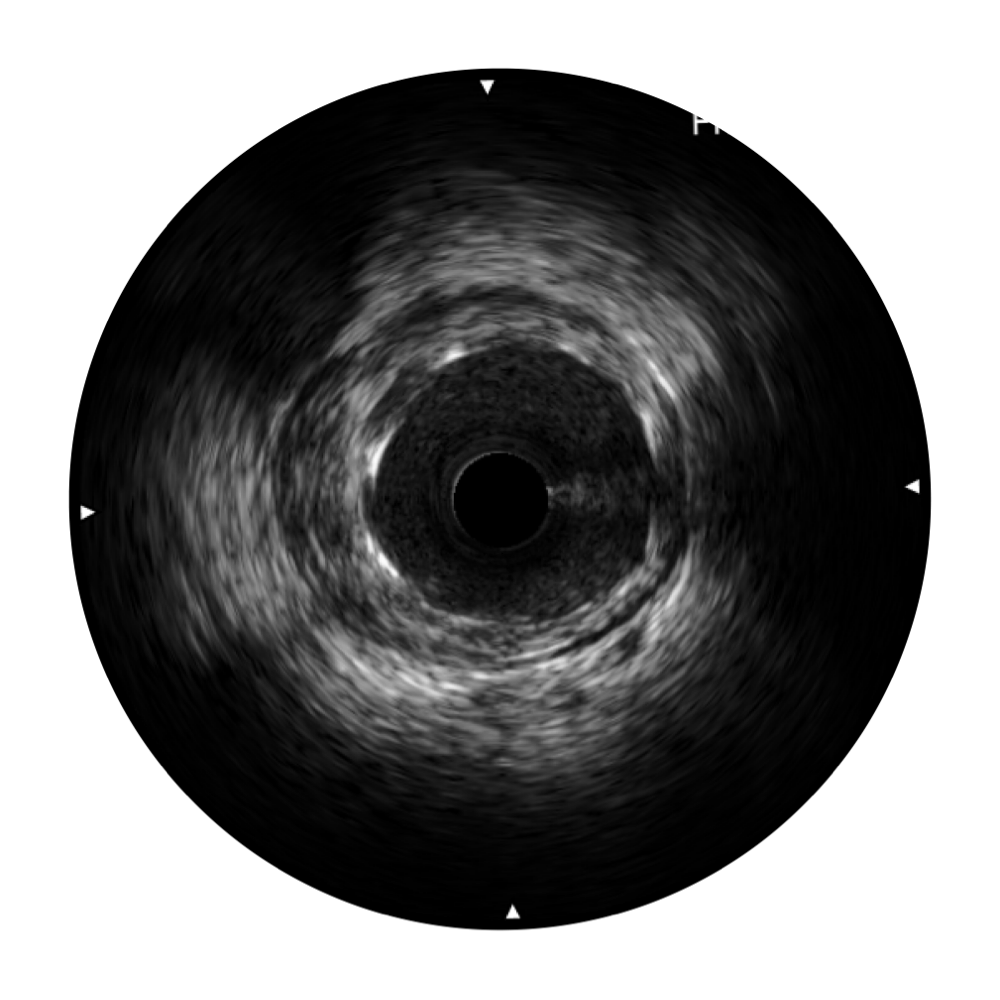

银河优越会宽频IVUS图像

对比传统IVUS导管成像,银河优越会宽频IVUS图像的近场支架梁显影更细腻,远场中膜外血管仍清晰可辨,兼顾远中近,兼顾分辨力与穿透深度